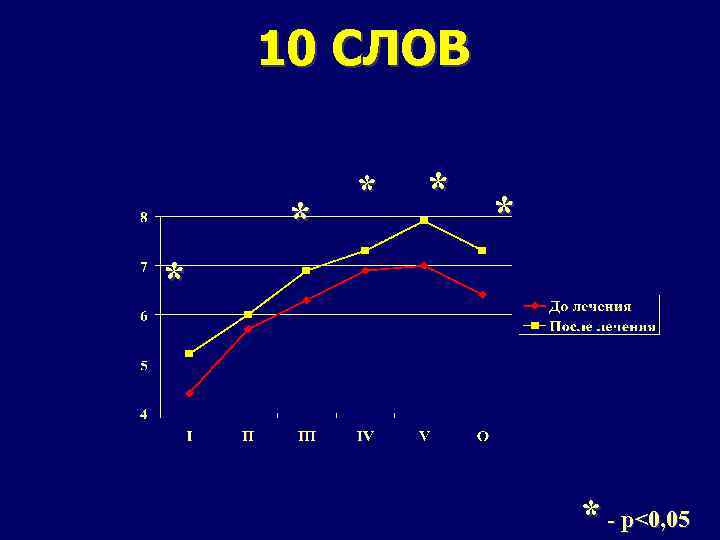

10 СЛОВ * * * - p<0, 05